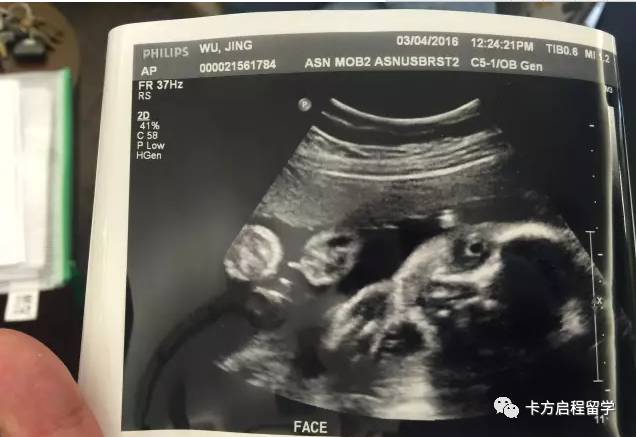

(本文图片来源于网络)